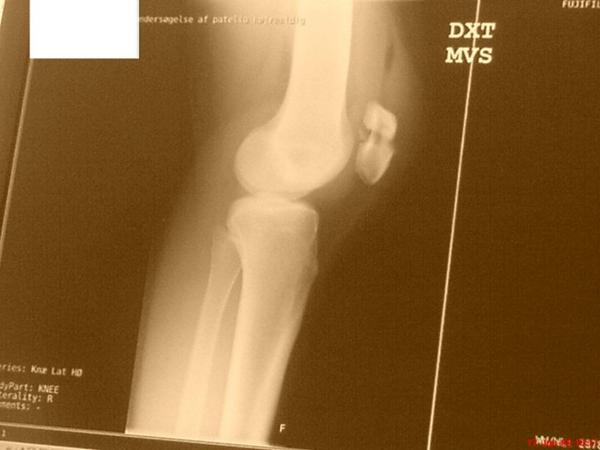

• #1   8. okt 2013 Da jeg på en ridetur blev sparket på knæet og fik åbent knæbrud smiley

• #13   8. okt 2013 her et billede derfra smiley

• #23   8. okt 2013 det er mit venstre ben der er kommet til skade. dette billede er taget en halv time efter faldet. ca.

• #25   8. okt 2013 Her er også et, faktisk næsten værre (selve oplevelsen) end da jeg brækkede knæet.

• #26   8. okt 2013 ^billeder er tager lige efter.. det blev meget meget sort